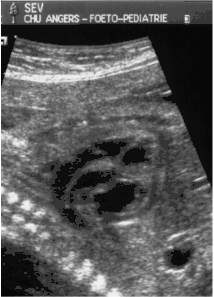

- le signe d'appel habituel est la perte du croisement des gros vaisseaux. Normalement, l'aorte et le tronc pulmonaire se croisent peu après leur sortie du cœur. Il est donc impossible de dérouler les deux vaisseaux sur un même plan de coupe. Quand l'aorte est vue longitudinalement, le tronc pulmonaire n'apparaît qu'en section transversale ("aorte en long, tronc pulmonaire en rond") et vice-versa. Dans la D-TGV simple, la plus fréquente, les vaisseaux ont un trajet parallèle et peuvent donc être visualisés longitudinalement simultanément.

- la confirmation est obtenue par l'analyse des gros vaisseaux et de leurs connexions aux ventricules. L'aorte est caractérisée par le fait qu'elle décrit une crosse, donne naissance aux vaisseaux à destinée céphalique et est le vaisseau qui monte le plus haut dans le thorax. Le tronc pulmonaire est caractérisé par sa bifurcation précoce en deux branches, les artères pulmonaires droite et gauche. Sur un cœur par ailleurs normal, le ventricule droit est situé en avant et à droite du ventricule gauche, le tronc pulmonaire est donc le vaisseau le plus antérieur. La TGV se caractérise par la position antérieure du vaisseau qui décrit la crosse et donne les vaisseaux céphaliques : l'aorte.